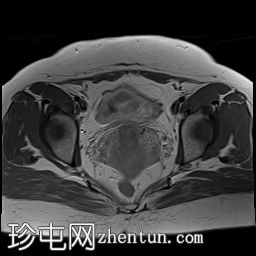

轴位

ADC序列

可见子宫外腹腔内妊娠囊,内含胎儿组织。

该妊娠囊向后推移子宫,并与剖宫产瘢痕凹陷处紧密相连。

该妊娠囊与相关肠袢无法分离。可见其与性腺血管密不可分,且性腺血管明显突出。

胎盘位于妊娠囊后方,紧贴子宫前壁。

沿妊娠囊下缘可见一处异质性局灶性积液,最大轴向尺寸约为 8.4 × 5.5 cm,T1 加权像呈异质性高信号,T2 加权像呈异质性中等信号,T1 脂肪抑制序列未见信号下降,提示为血液成分。该积液压迫膀胱。

可见周围脂肪间隙呈条索状改变。

左侧卵巢无法辨认。

右侧卵巢未见实性或囊性肿块。

子宫体积增大,后倾,子宫内膜厚度约 1 cm,子宫下段前壁可见局灶性变薄(既往子宫瘢痕)。子宫连接区完整,未见肌层肿块。可见子宫内膜腔边缘有血性分泌物。